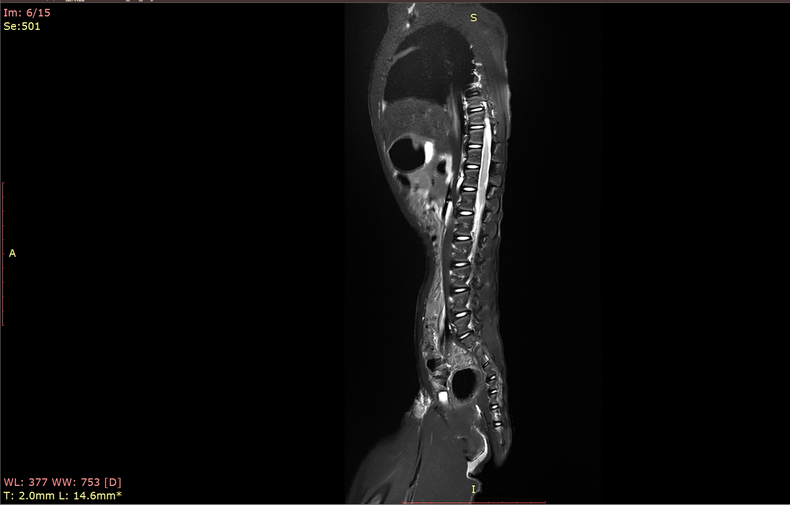

预定本数据集为收集到的2023年中国科学院昆明动物研究所实验动物中心5只北平顶猴(青年,雌性2只6-8岁,雄性3只7-9岁)的脊柱核磁共振扫描数据,主要扫描序列为T2w等。通过该数据可进一步了解到健康青年北平顶猴脊柱影像学特征,并为未来的研究提供重要的依据。

a.物种:北平顶猴

b.实验动物信息

样本数量:5只

年龄分布:6-9岁

重量分布:6-11kg

性别分布:雌性2只,雄性3只

c.扫描仪规格

扫描仪类型:联影uMRNX 3.0T磁共振扫描仪器

线圈:超柔线圈和体线圈

d.扫描程序

动物福利伦理:由中国科学院昆明动物研究所实验动物福利伦理委员会批准

动物护理和饲养:中国科学院昆明动物研究所实验动物中心

麻醉程序:丙泊酚维持麻醉

扫描体位:仰卧位